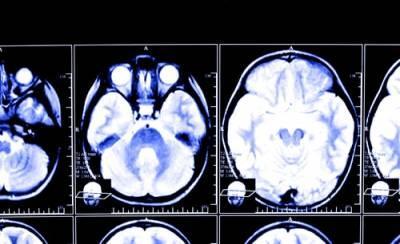

According to a study published in the journal Neurology, even relatively minor brain injuries carry an increased risk of developing Parkinson’s Disease, a neurodegenerative disorder.

Researchers studied 325,870 veterans whose health data was recorded from 2002 to 2014 to explore the correlations between traumatic brain injuries (TBI) and the development of Parkinson’s Disease. Of those who developed Parkinson’s Disease, 65% percent had previously had a TBI ranging from mild to severe in nature.